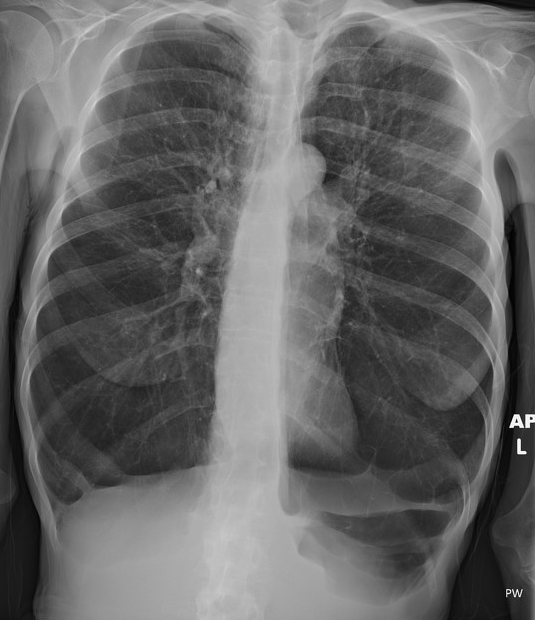

68세 남성이 숨이 차다며 내원하였다. 40년의 흡연력이 있다. 기침과 묽은 가래가 나오고, 걸을 때 숨 차는 증상이 더 심해진다고 한다. 지난 4년 동안 증상이 간헐적으로 나타났다고 한다. 활력징후는 혈압 135/85 mmHg, 맥박 98/분, 호흡수 22/분, 체온 36.7도였다. 비강 캐뉼라로 산소 4L를 투여한 후 시행한 동맥혈 가스분석 결과는 다음과 같다. 진단은?

• 50년의 흡연력과 기침, 가래, 호흡곤란 증상이 있고, 검사실 검사 상 호흡성 산증 소견, 흉부 X선상 폐기종 소견이 관찰되는 COPD가 의심되는 환자이다.

• X선 사진에서 diaphragm이 flattened되어 lung이 hyperinflated되어 있는 양상이 관찰되므로, 폐기종이 정답이다.

• Chest X-ray 사진만 보더라도 쉽게 정답을 유추할 수 있어야 한다.